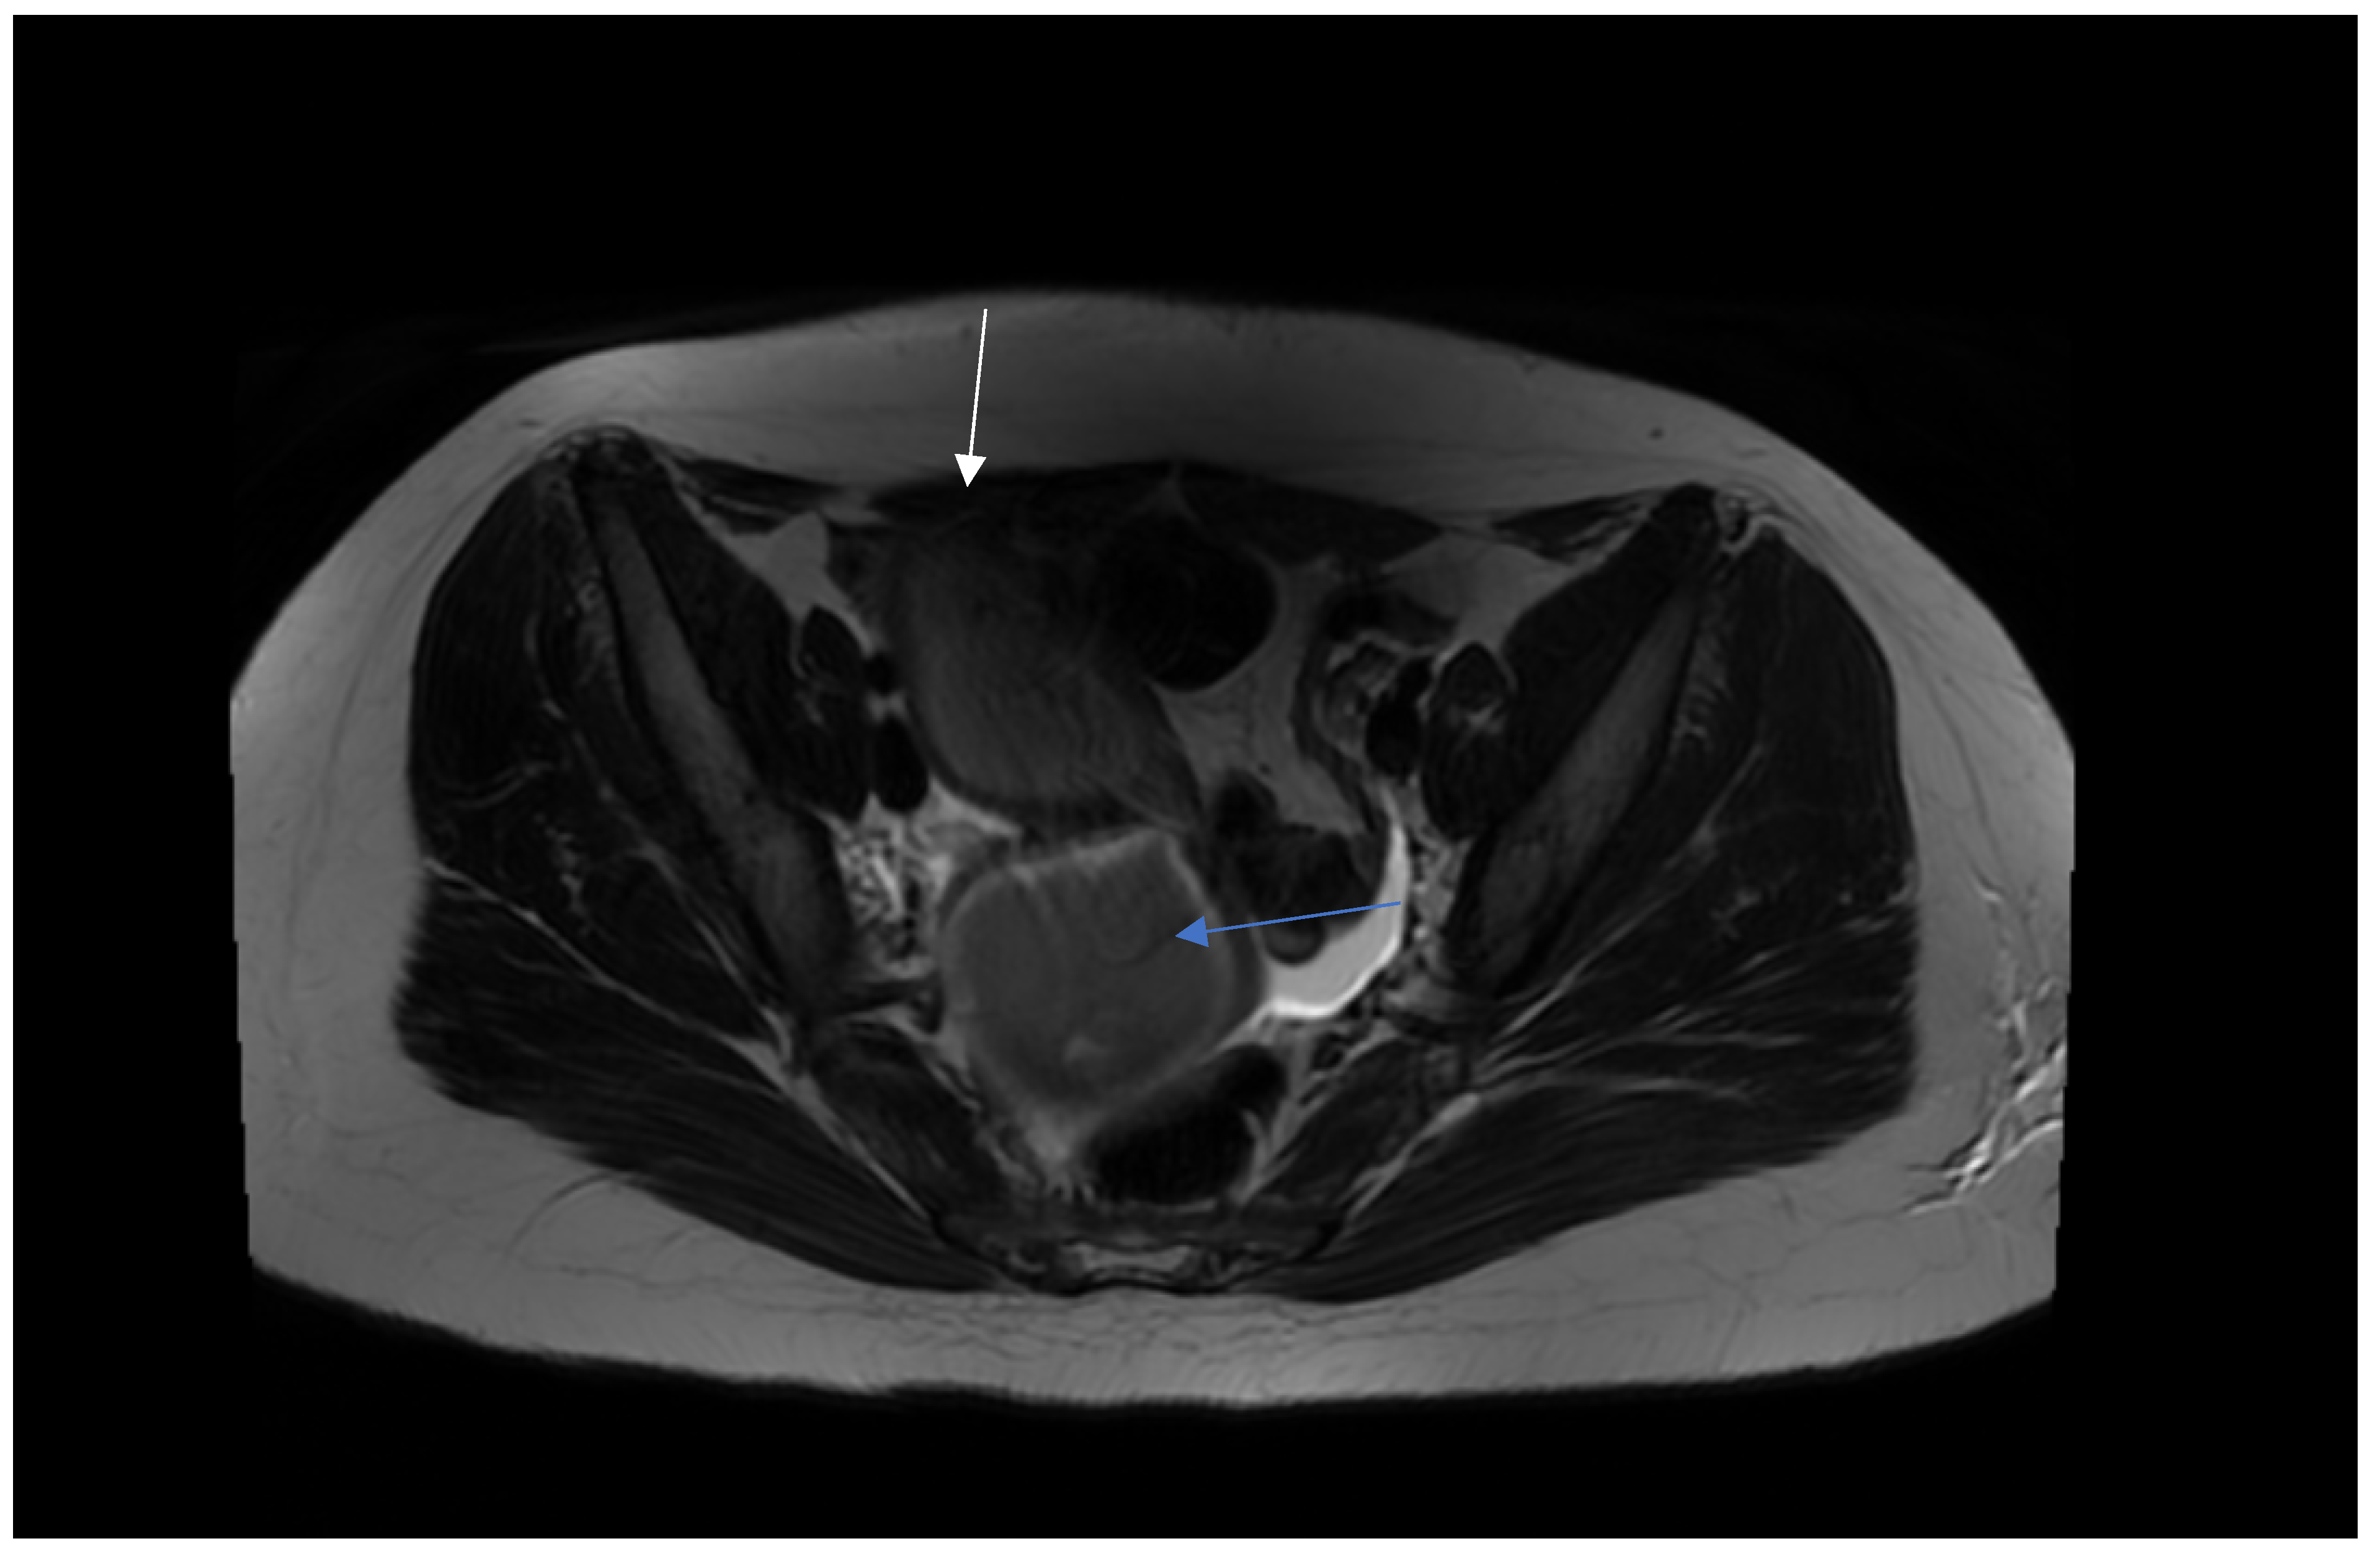

2.2. Preoperative Management